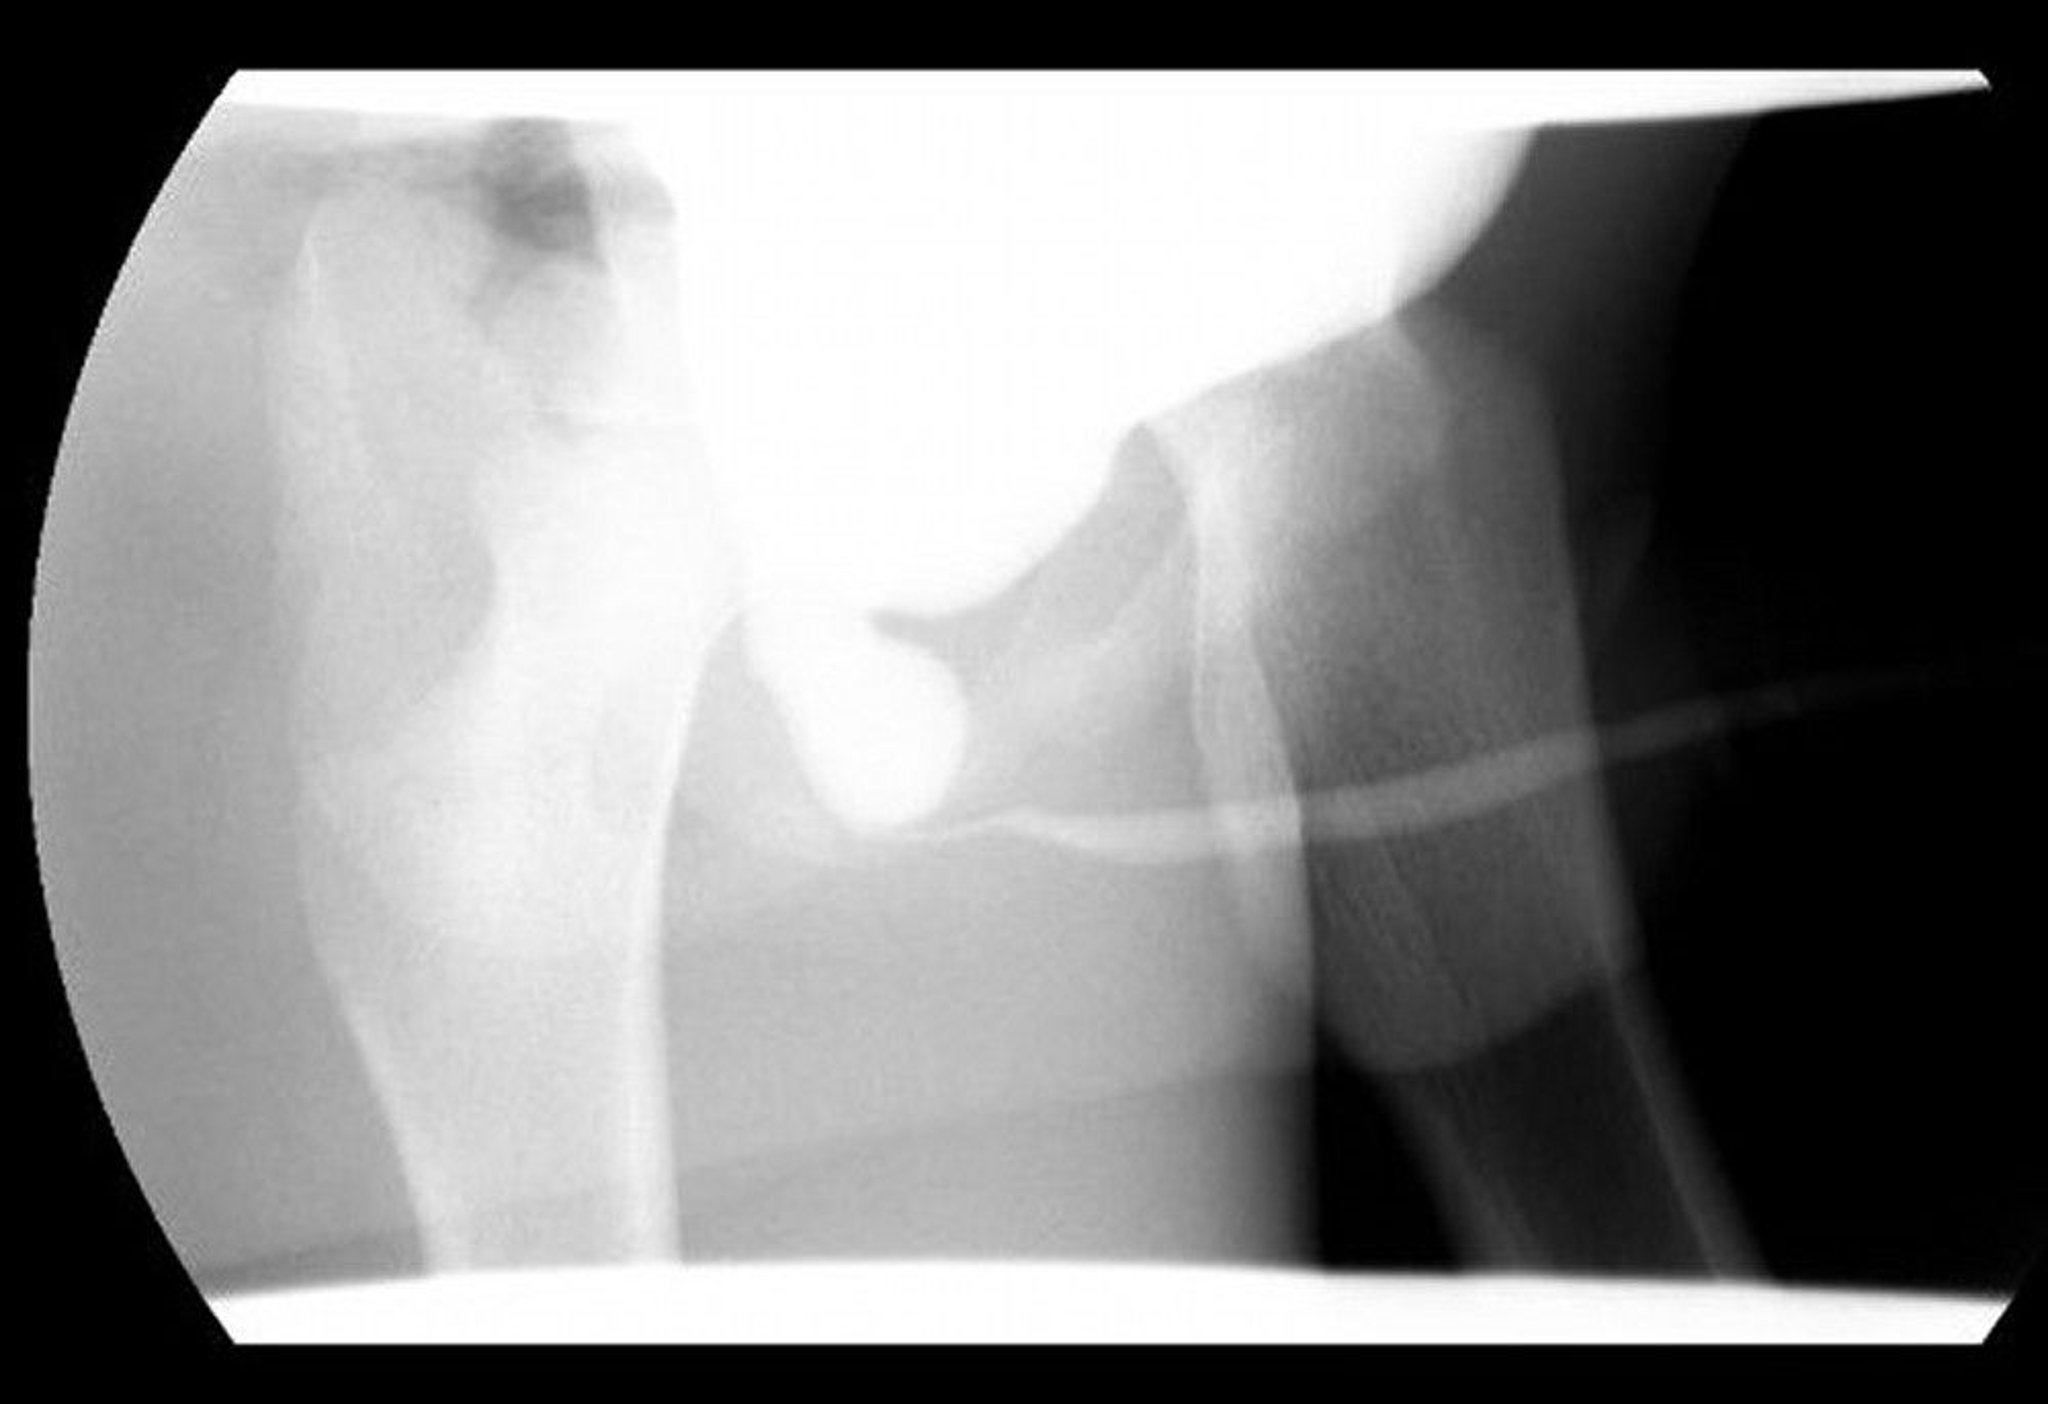

This voiding cystourethrography (VCUG) image shows a dilated posterior urethra with distal obstruction due to posterior urethral valves.

Image courtesy of Drs. Ronald Rabinowitz and Jimena Cubillos.